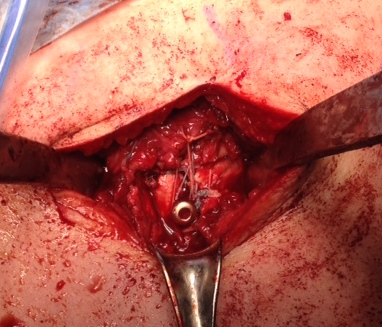

proximal humerus fracture Background ORIF with locking plate Arthroplasty Greater tuberosity fractures Lesser tuberosity fractures / avulsions Book traversal links for Proximal humerus fractures ‹ Pectoralis Major Tears Up Background ›